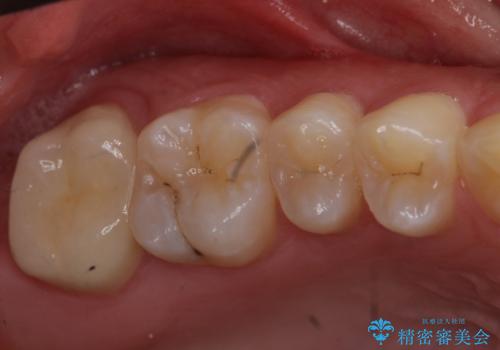

- 奥歯が虫歯になり、位置的に詰め物は難しかったため、被せものにする治療を行いました。

- 11万円 ジルコニアクラウンスタンダード10万円、仮歯1万円費用は治療当時の料金となります

頬側に咬頭が一つ多い歯であったのと、歯肉に近い位置が虫歯になっていたため、被せものでしっかり覆う治療を行いました。